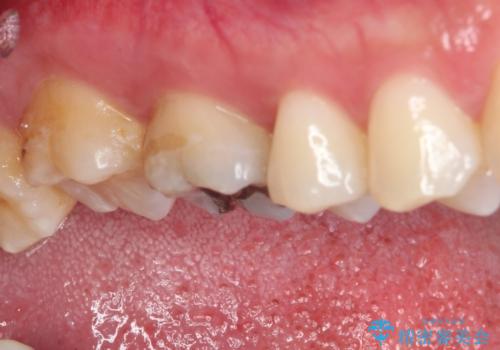

- 銀歯をセラミックにしたいとのことで来院された患者様です。

まず麻酔をして銀歯を外し、むし歯を除去し、形を整えて型取りします。

そして次の来院時、セラミックインレーを装着し、噛み合わせなどの調整を行います。

それを左右に分けて行いました。

インレーを装着するときは、唾液や血液による接着力の低下を避けるためにラバーダム防湿を行いました。